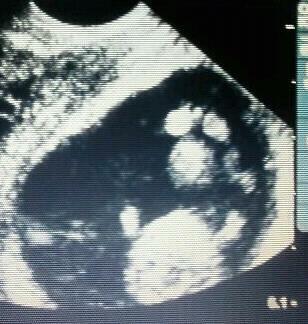

This is the closest side view I have... Attachment 7109

I cant tell sorry